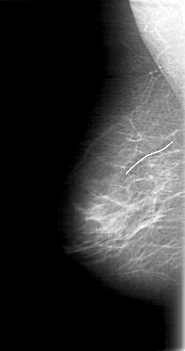

D_4073_1.RIGHT_MLO

LESION_TYPE MASS SHAPE OVAL MARGINS OBSCURED

ASSESSMENT 0

SUBTLETY 4

PATHOLOGY BENIGN